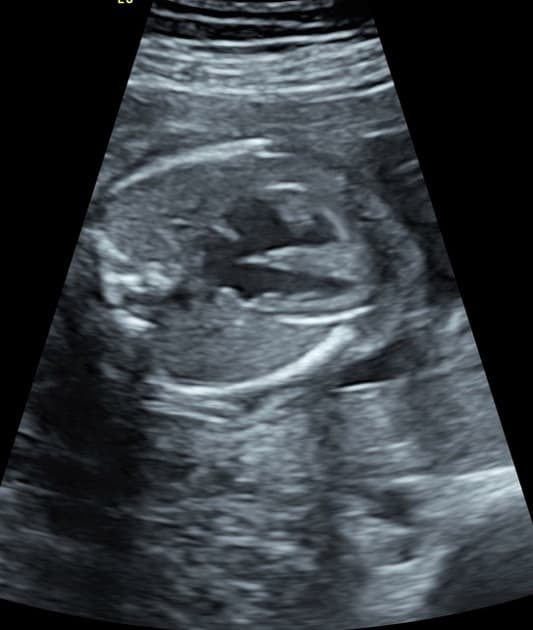

- Động mạch phổi ôm quanh động mạch chủ – thủ thuật LeCompte.

- Hai động mạch vành xuất phát từ mấu động mạch vành phải, một động mạch vành xuất phát từ mấu trái.

Chuyển vị đại động mạch (transposition of the great arteries) đã được phẫu thuật sửa chữa lúc nhỏ bằng thủ thuật đảo động mạch (arterial switch procedure).

Chuyển vị đại động mạch đã được phẫu thuật sửa chữa (surgically corrected transposition of the great arteries)

- "Thủ thuật LeCompte gồm việc đặt lại động mạch phổi phía trước động mạch chủ mà không cần ống nối, thường thấy sau thủ thuật đảo động mạch."

Chuyển vị đại động mạch đã được phẫu thuật sửa chữa là tình trạng bệnh nhân từng trải qua phẫu thuật đảo động mạch (ASO) lúc nhỏ để khôi phục sự nối thông bình thường giữa thất và động mạch. Thủ thuật LeCompte, trong đó động mạch phổi được đặt phía trước động mạch chủ mà không cần ống nối, là dấu hiệu đặc trưng của phẫu thuật này. Các hình ảnh học cho thấy vị trí trước và lệch phải của động mạch chủ mới (trước đây là thân động mạch phổi) và động mạch phổi mới đi phía sau, lệch trái. Việc cấy ghép lại động mạch vành là bước then chốt, và các dị dạng như động mạch vành đơn hoặc đi trong thành động mạch làm tăng độ phức tạp phẫu thuật. Biến chứng lâu dài bao gồm giãn gốc động mạch chủ mới, hẹp động mạch phổi và hẹp lỗ động mạch vành, đòi hỏi theo dõi suốt đời.